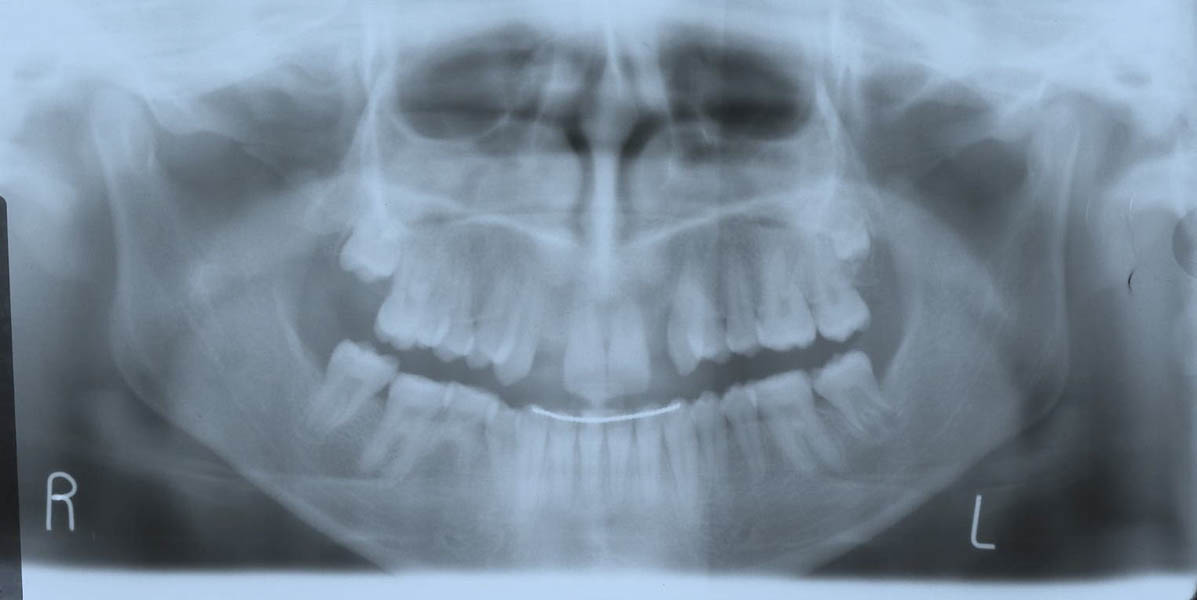

A doua etapă a tratamentului a fost amânată până în aprilie 2006, când pacienta a împlinit vârsta de 11 ani şi 5 luni. În acel moment, fetiţa prezenta erupţie şi dezvoltare radiculară adecvată, astfel că aparatele fixe aplicate acum n-ar fi purtate o perioadă îndelungată. Ocluzia inversă frontală şi angrenajul invers lateral fuseseră corectate; totuşi, exista o diastemă mare, în principal cauzată de lipsa incisivilor laterali superiori (fig.3). În acest moment, radiografia panoramică relevă anodonţia incisivilor laterali maxilari şi a premolarului secund drept mandibular, o anatomie redusă a rădăcinilor incisivilor centrali superiori, incluzia caninului superior stâng şi dezvoltarea întârziată a rădăcinii celui de-al doilea premolar inferior (fig. 4).